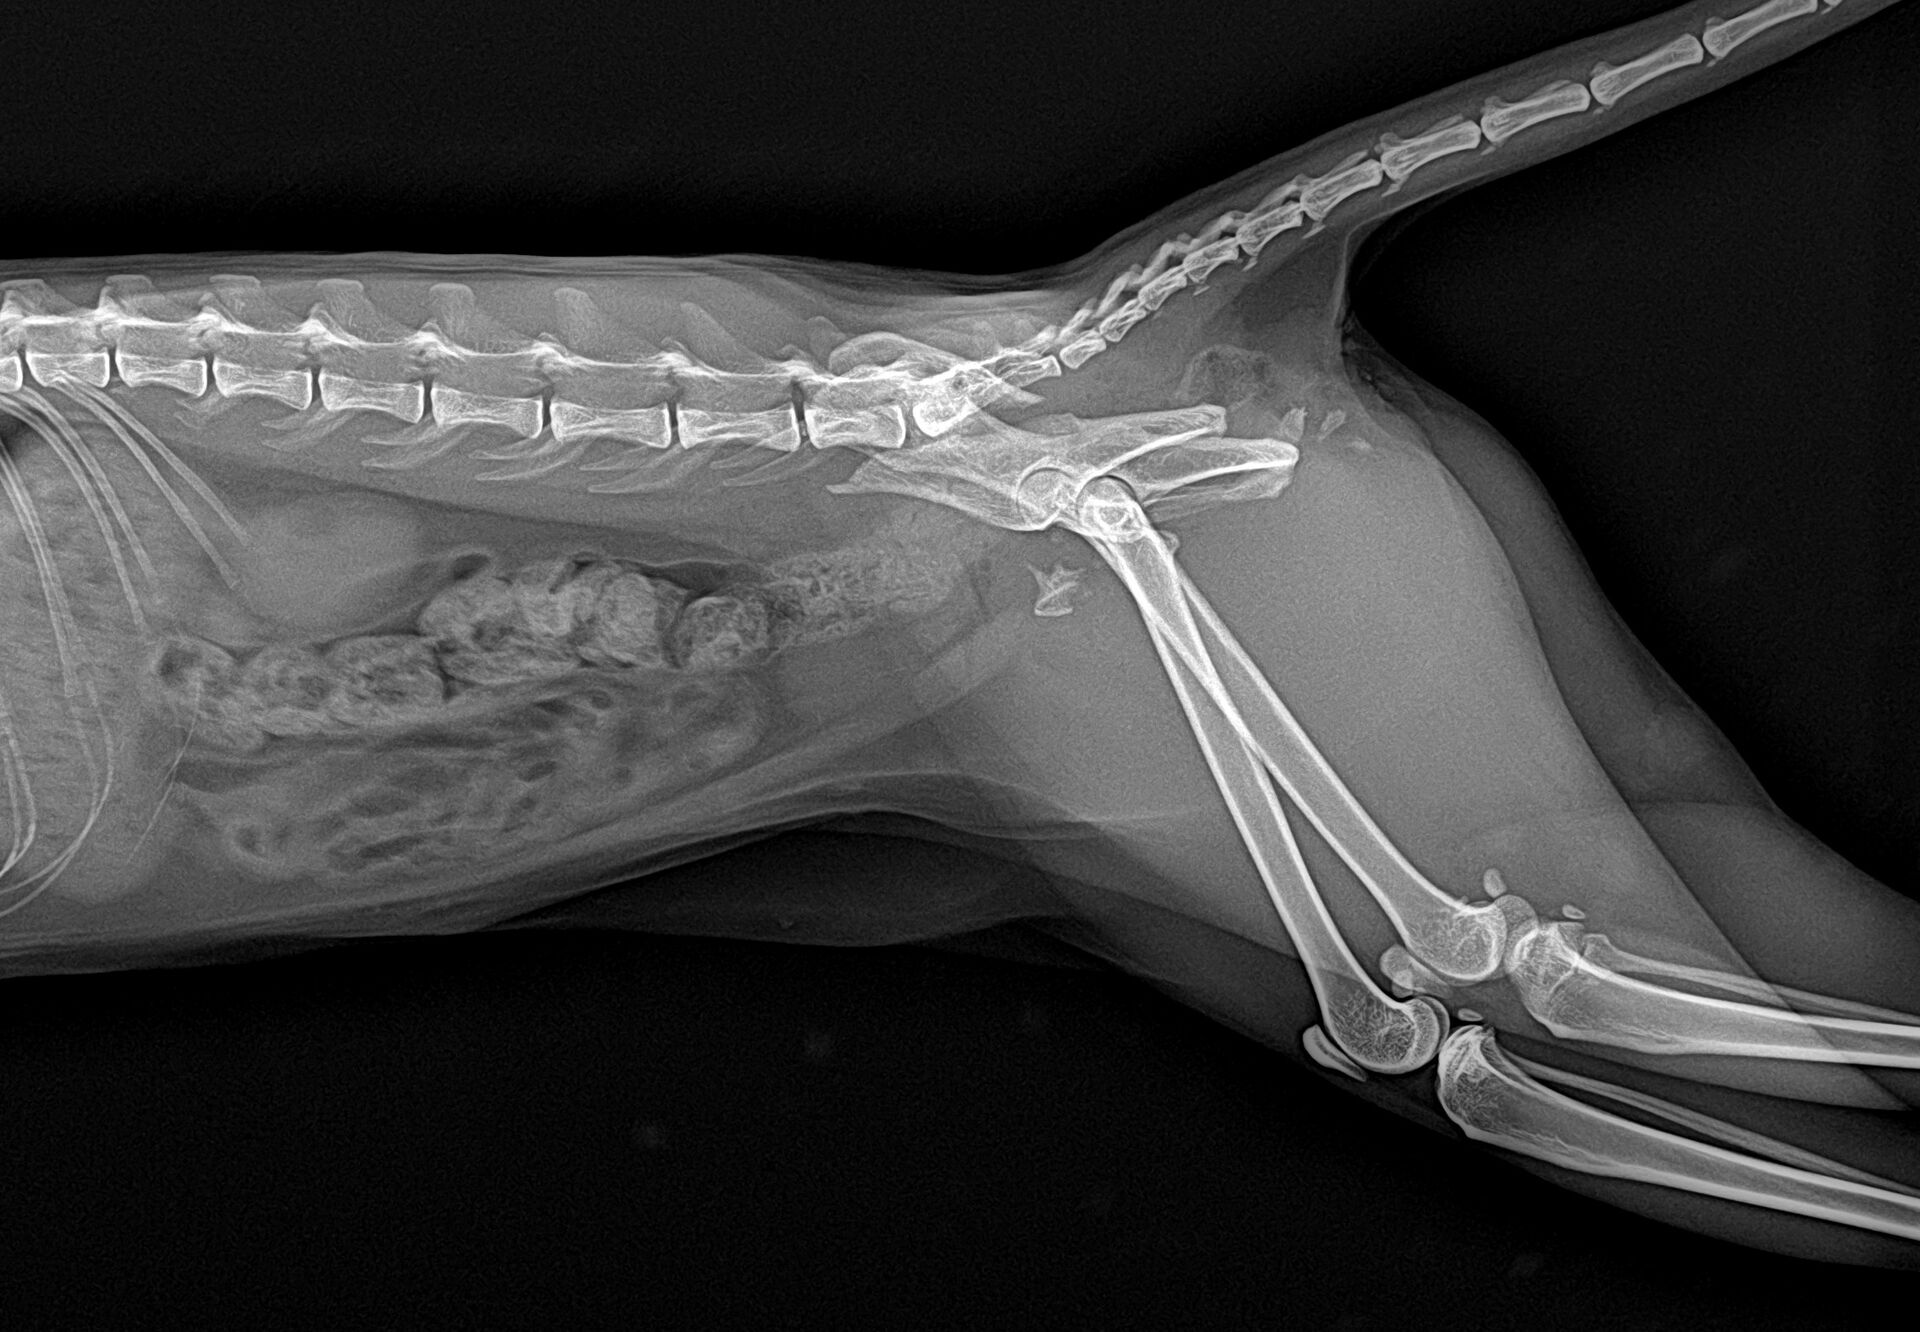

まずはレントゲンを撮りました。それが以下の写真です。

左側の骨盤(腸骨と座骨)が骨折しています。幸い仙腸関節は問題ないかと思われました。